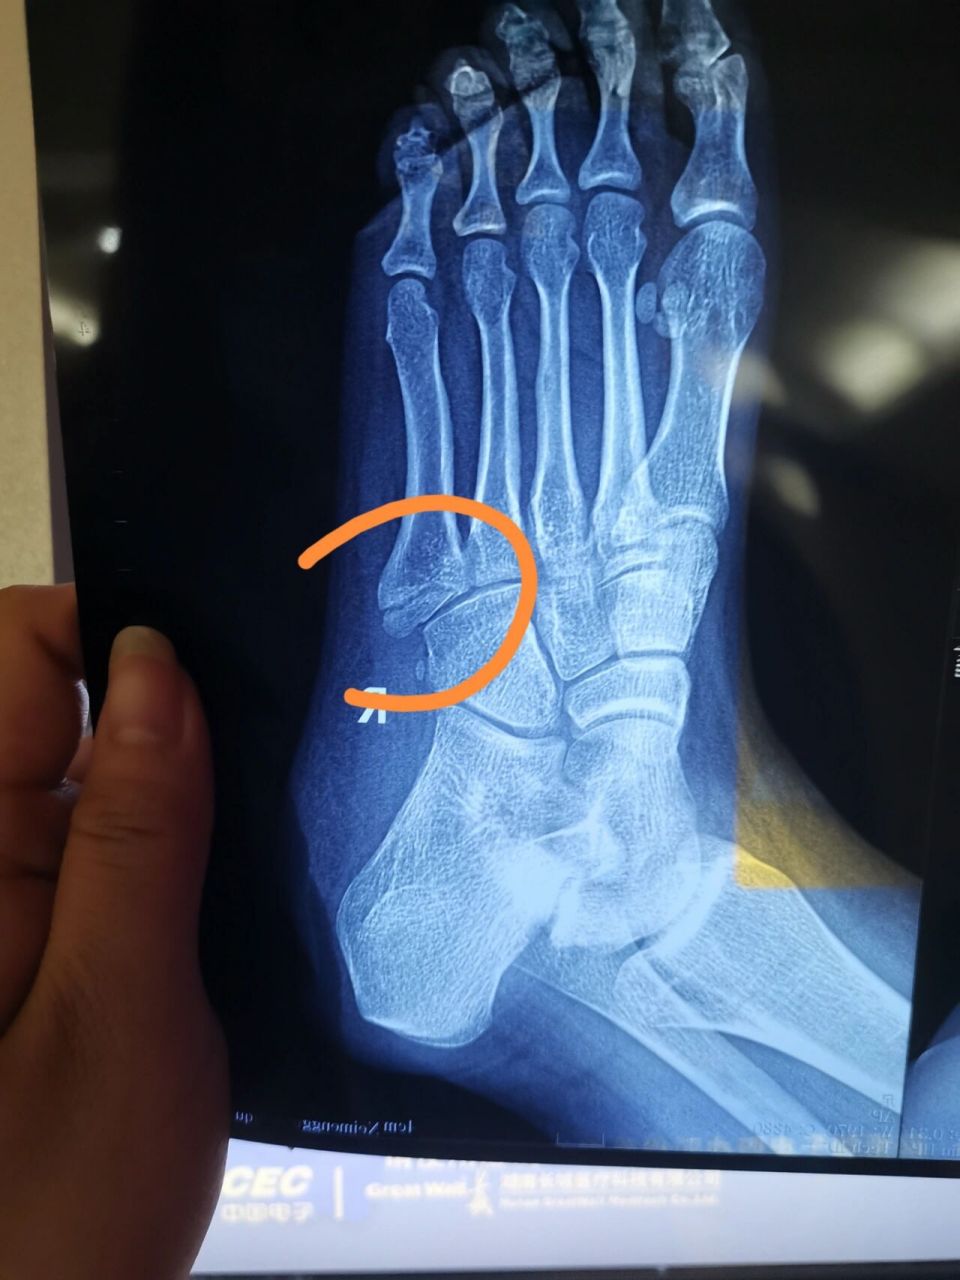

左脚第五跖骨基底部骨折需要几个月恢复

第五跖骨基底骨折2个月康复